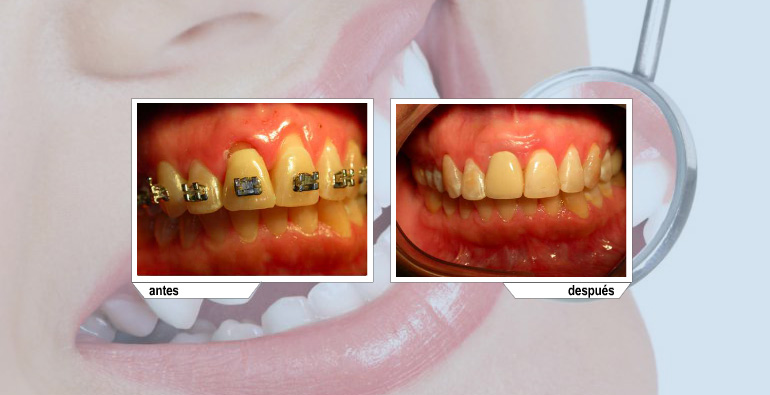

Este tratamiento se utiliza para cubrir raíces expuestas, con eso evitamos sensibilidad y posibles caries radiculares.

Son utilizados principalmente para ganar encía queratinizada.